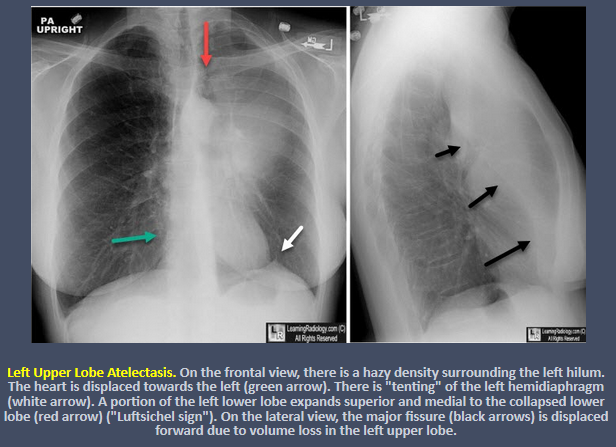

What are the signs of left upper lobe atelectasis?